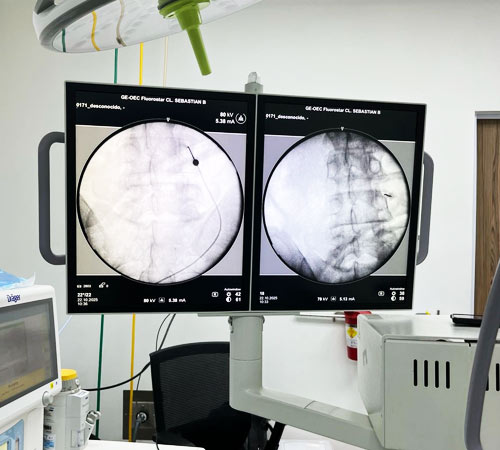

El procedimiento se realiza en un ambiente estéril utilizando ayudas radiológicas (rayos X) para localizar con precisión el nervio afectado. El procedimiento dura entre 30 – 60 minutos y se realiza en forma ambulatoria, por lo que el paciente regresa a casa el mismo día.